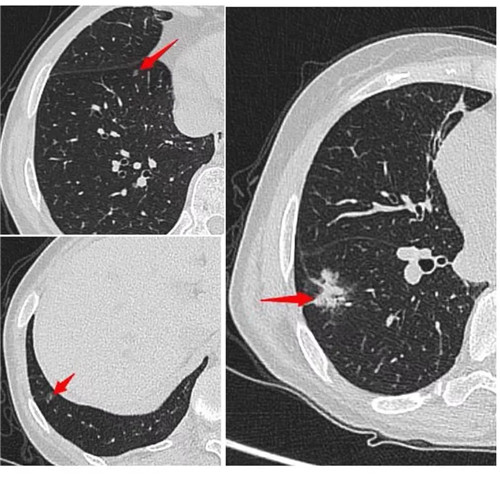

經(jīng)過術(shù)前充分評估,崔凱主任決定一次手術(shù)同期為患者切除雙肺總共六枚結(jié)節(jié)。手術(shù)團(tuán)隊?wèi)?yīng)用minics肺結(jié)節(jié)三維重建分析及術(shù)前CT引導(dǎo)下錨針穿刺定位等先進(jìn)工具,精準(zhǔn)定位患者雙肺的6枚磨玻璃結(jié)節(jié),其中最大的2cm,最小的0.6cm。

術(shù)前各項準(zhǔn)備完畢,崔凱主任為患者行“單孔胸腔鏡右肺下葉切除術(shù) 淋巴結(jié)清掃術(shù) 單孔胸腔鏡左肺上葉尖后段切除術(shù) 左肺下葉背段切除術(shù) 淋巴結(jié)清掃術(shù)”,一次手術(shù)成功將患者兩側(cè)肺部6枚結(jié)節(jié)全部切除,術(shù)后病理結(jié)果提示六枚結(jié)節(jié)均為早期肺癌。